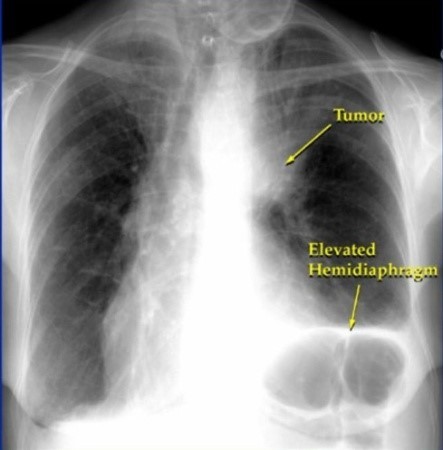

호흡 곤란 및 숨 가쁨

- 설명: 암이 커져 기관지를 막거나 폐의 기능을 저하시키면, 조금만 움직여도 숨이 차고 답답한 느낌이 들 수 있습니다.